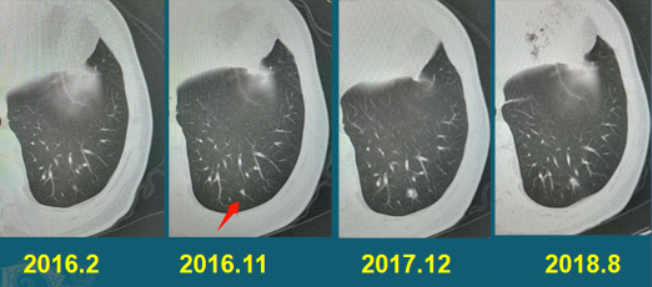

病例2:肺鳞癌 3年零10个月

68岁老人,老烟民,因为冠心病住院,首次胸部CT看不到明显异常,之后逐渐出现肺结节

在9个月时间里长出3mm肺结节,又隔了13个月,增大到8mm,之后再过了8个月,结节却萎缩变小了一点(大约7mm)。随访过程中逐渐增大的肺结节,要提升危险等级,积极处置。

有的肺结节暂时性缩小并不提示良性,之后过了1年零2个月,它猛然增大成一个不规则肿块,直径3cm,表面有分叶,并且牵拉胸膜了。

一年多的时间快速增大,提示肿瘤已经进入加速期,这时候如果继续放任不管,肿瘤会展露凶残的真面目!只过了2个月,肿瘤再次以肉眼可见的速度增大,并且发生了胸膜结节状转移(下图蓝箭头),病理穿刺是低分化肺鳞癌。